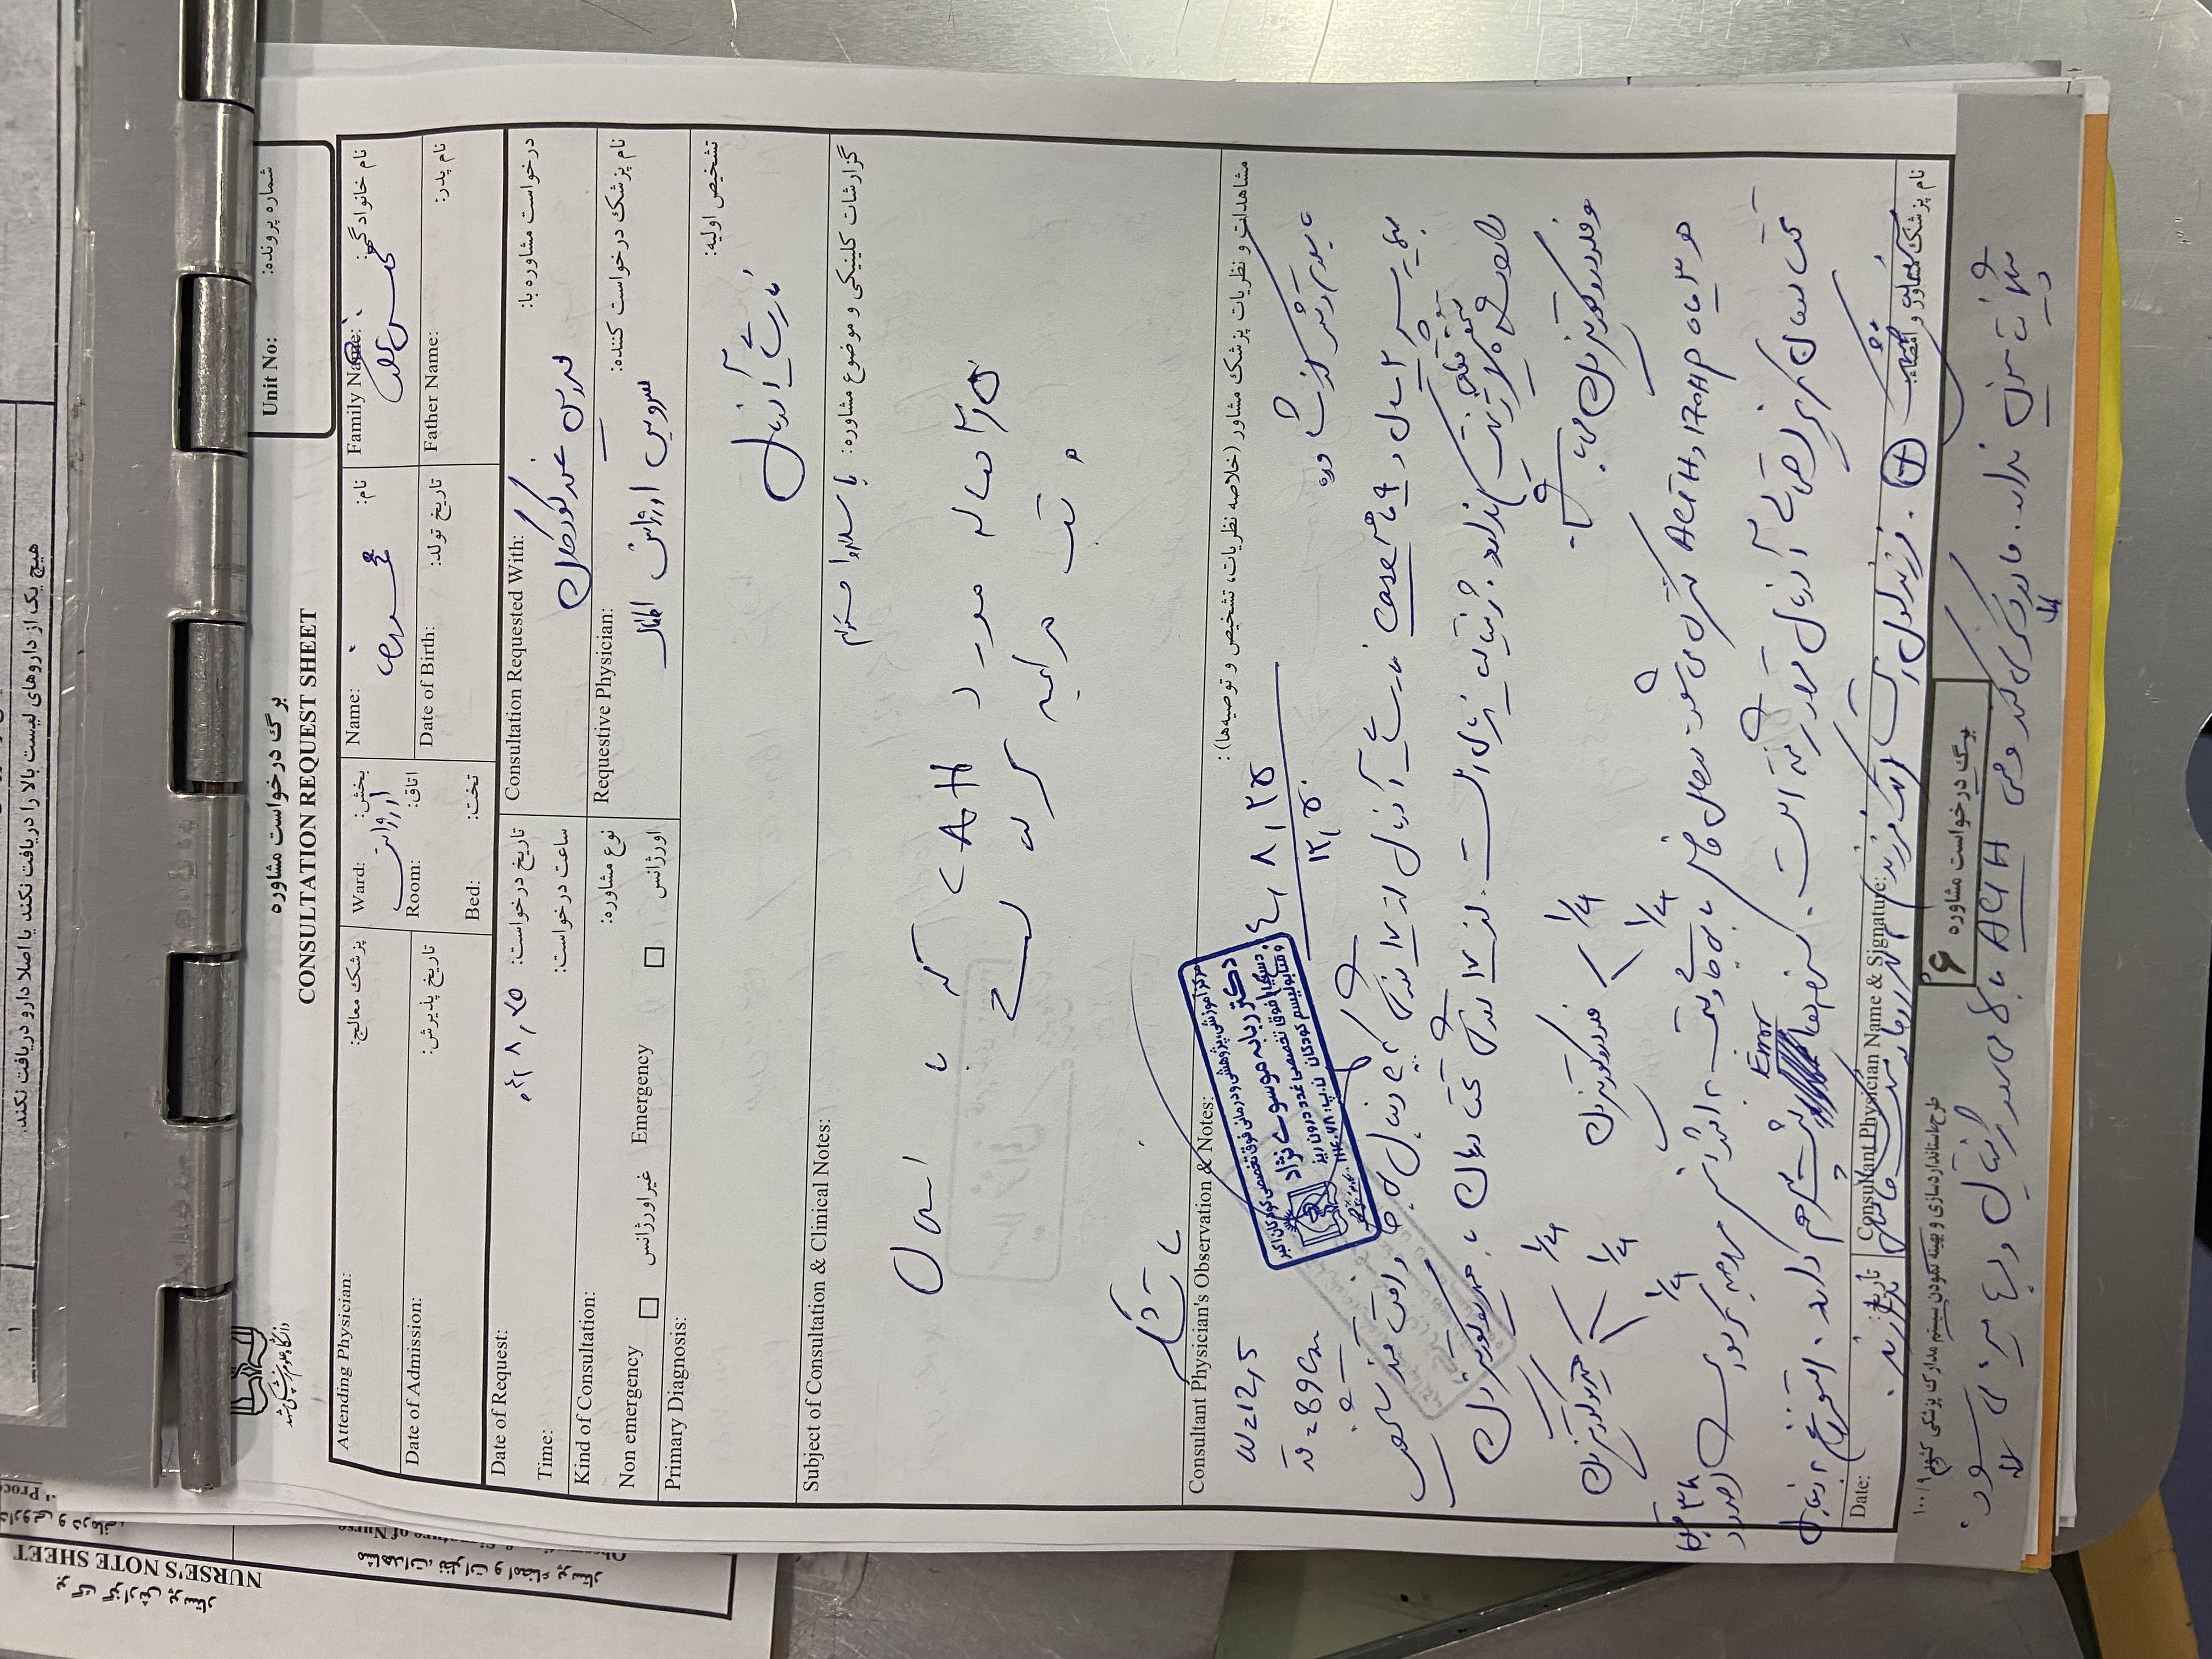

بیمار پسر ۲ سال ونه ماه مورد cah از ۱۷ روزگی تشخیص شده (با علایم اولیه poor feeding و تیرگی پنیس و لب وپتاسیم ۹ )با سرفه prوتب از دیشب شروع شده به اورژانس مراجعه کرده وهمچنین ۳ نوبت استفراغ داشته وابریزش بینی وسایقه بستری مکرر داشته با شک به گریز ادرنال بستری شدن

Cah از بدو تولد

/سالی ۴ بار بستری به علت cah/

زردی نوزادی/

ترم/ تک فرزند/زایمان طبیعی / واکسیناسیون کامل /

وزن تولد ۳٫۲ کجم/ وزن الان ۱۳کیلو/ قد ۸۹/

zscore 0.7/

هیدروکورتیزون ۱۰ میلی

هر ۸ ساعت

فلودروکورتیزون هر ۸ ساعت / دوز دوبرابر شده بعد از بروز علایم

پسر 2ساله ونه ماه با تب وسرفه وابریزش و۳ بار استفراغ از دیشب به اورژانس مراجعه کرده مورد cah از ۱۷ روزگی تحت درمان با هیدروکورتیزون و فلودروکورتیزون بوده با شک به کریز ادرنال بستری شدن تاکی پنه وتاکی کاردی داشته